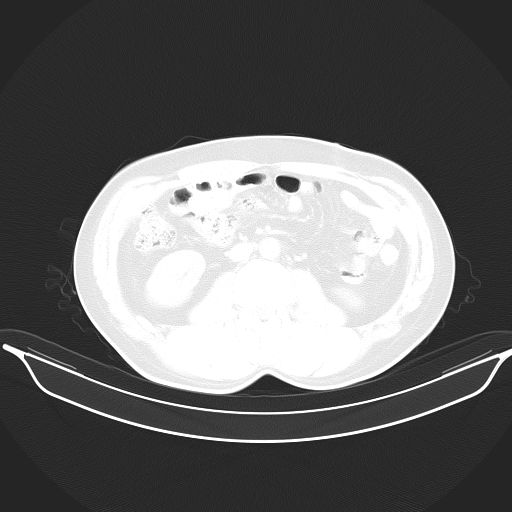

转移性肺肿瘤不排除,建议结合相关检查考虑

1、均为转移,原发灶不在肺内。2、肺癌肺转移。